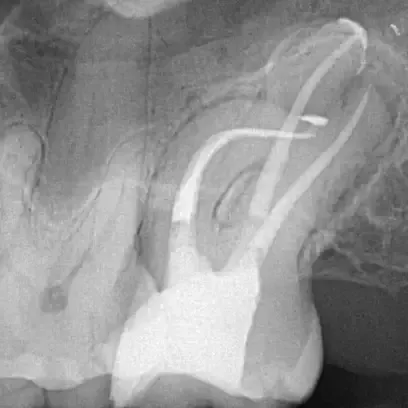

Fall 1: Revisionsbehandlung

Ausgangssituation

Kontrolle nach Wurzelfüllung